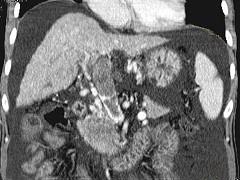

问题 女性,50岁,曾患乙型肝炎,肝硬化多年,右上腹胀痛1月余,CT检查如图所示,最全面的诊断是 ( )

选项 A.肝硬化、腹水伴胆管细胞癌 B.肝硬化、腹水伴原发性肝癌 C.肝硬化、腹水、肝癌并门脉癌栓 D.肝硬化、腹水并肝脓肿 E.肝硬化、腹水并肝血管瘤

答案 C